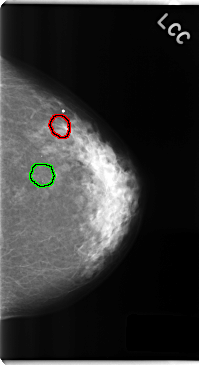

FILE: C_0247_1.LEFT_CC.OVERLAY

TOTAL_ABNORMALITIES 2

ABNORMALITY 1

LESION_TYPE MASS SHAPE ROUND MARGINS CIRCUMSCRIBED

ASSESSMENT 3

SUBTLETY 4

PATHOLOGY BENIGN

TOTAL_OUTLINES 1

BOUNDARY

ABNORMALITY 2

LESION_TYPE CALCIFICATION TYPE AMORPHOUS DISTRIBUTION CLUSTERED

ASSESSMENT 4

SUBTLETY 3